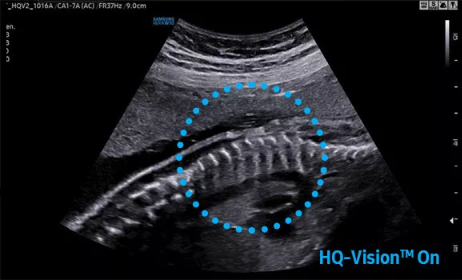

2D成像方面,Hera i10集成了包括ShadowHDR?、HQ-Vision?、ClearVision等多項具有三星“血統(tǒng)”的技術(shù),加強(qiáng)了圖像的陰影抑制、減少偽影、緩和模糊區(qū)。